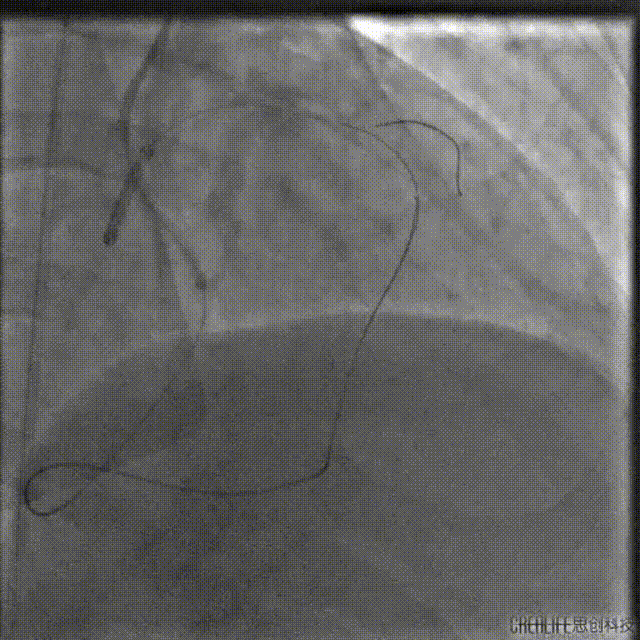

再次尝试正向开通

通过双腔微导管送入P200导丝Kissing逆向导丝,最终在肝位Kissing进入LAD远段。

送入2.0*20mm球囊对病变段进行扩张。

再次送入IVUS超声导管至LAD远段回撤,结果显示导丝全程位于真腔,近端见钙化及少量血肿。

由远及近串联植入2.5*36mm、2.75*36mm、3.5*29mm支架三枚。

支架释放后造影,中段支架膨胀欠佳。